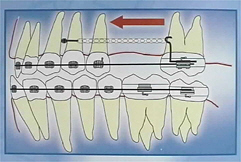

Pin Pin

Pin

Insbesondere bei der Behandlung von Erwachsenen bietet dieses Verankerungssystem eine wertvolle compliance-unabhängige und positionsstabile Verankerungsalternative.Durch diese Verankerungsimplantate ergeben sich völlig neue Behandlungsmöglichkeiten vor allem im Bereich der Erwachsenenbehandlung und der präprothetischen Konzepte.